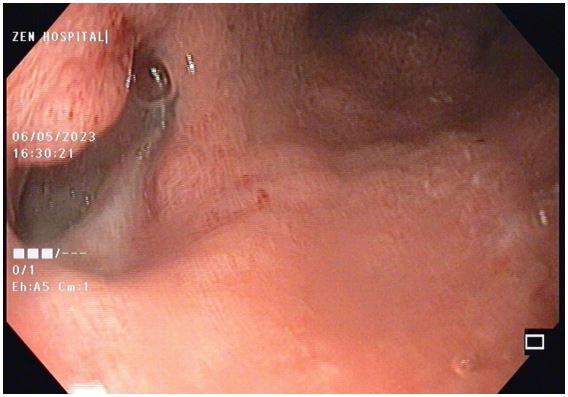

A 65 year lady a case of squamous cell carcinoma of lower end of oesophagus, she has received neoadjuvant chemoradiotherapy and underwent total esophagectomy and gastric pull up, 2 weeks later she presented with fever and shortness of breath after routine work up CECT chest and upper abdomen was done s/o 7mm defect in posterior wall of pulled up stomach at the level of D 6 vertebra with the leak of oral contrast forming a 6.5 x 2.2 x 1.2 cm collection in right paravertebral region from D5 to D8 vertebral level. She was treated with IV antibiotics and other supportive measures. Upper GI endoscopy showed a large fistulous opening with an overlying slough in the posterior wall of the pulled-up stomach along the staple line (Figure 7). She continued to have a fever, so CT-guided pigtailing was done, and pus was sent for Culture sensitivity, and antibiotics were changed according to it. One week after the procedure, a repeat CECT chest and upper abdomen was done. The previously seen right posteromedial collection showed a decrease in size, but a contrast leak persists. She was continued with antibiotics and supportive measures. Her fever subsided, but for persistent fistulous openings, therapeutic options were excision of the stomach, esophagotomy, and covered stents. For the present case, we went ahead with indigenously modified E-Vac therapy, which was performed for a total of 26 days while the sponge was changed four times. During the first three changes, the sponge was placed directly into the cavity. Excellent granulation of the tissues around the leak was achieved, together with a progressive reduction of the cavity size and of the pleuro-mediastinal abscess (Figure 8). Daily output from the collection bag dropped After 6 weeks of initiation of the E-vac therapy, the cavity showed complete healing, a CT scan showed a small pseudodiverticulum but no leak, and she was started on a full oral diet.

Figure 8: Endoscopic image Anastamotic site leak with overlying slough in cavity after gastric pullup.

Figure 9: Endoscopic image of Healed cavity of gastric leak after E Vac therapy.